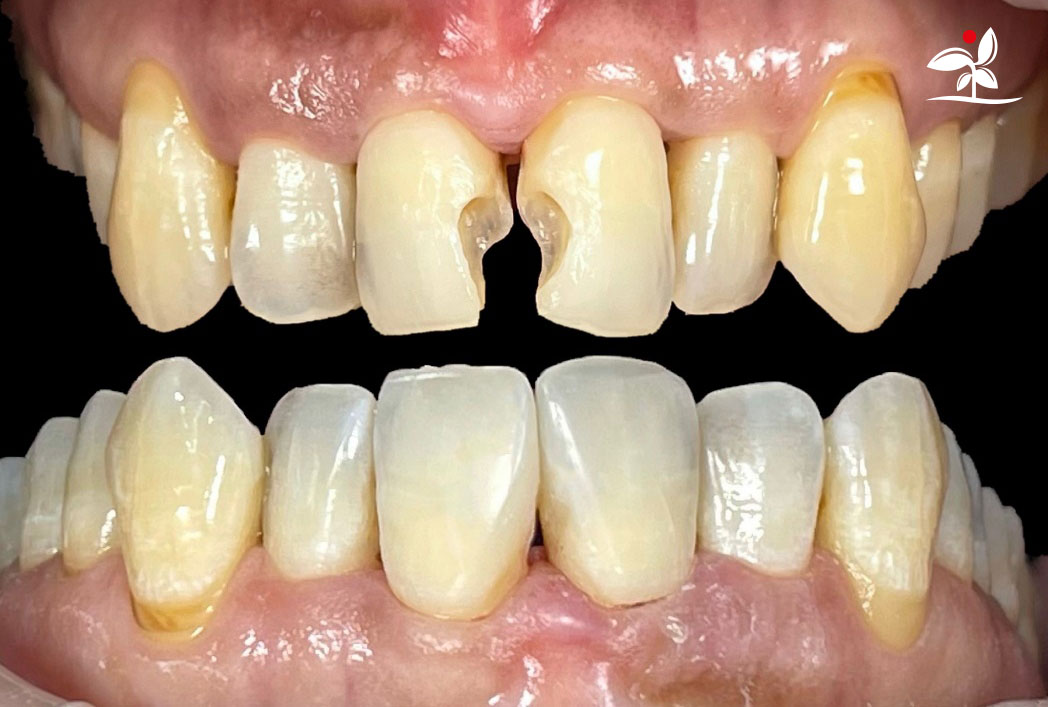

Restoration of Class IV Lesions using Naturomimetic Layering Technique (NLT) and Bioactive Restorative Materials

With the growing awareness about the health, function and aesthetic benefits of preserving natural tooth structure, patients are now globally demanding for aesthetic dentistry with minimally invasive procedures that has a low biological cost. This public demand has encouraged logical clinicians to adopt to the minimally invasive cosmetic dentistry (MiCD) concept and its treatment protocol [1] in their practice. The author has been using MiCD concept and its treatment protocols since 2017, which

include the methods of treatment that are simple, fast, predictable and healthy. In aesthetic restoration, the tooth color restorative materials placement technique is one of the most challenging, confusing and frustrating areas to learn owing to the multiple techniques that have been proposed by many clinicians and replicating such techniques in practice is not always as easy as they are marketed in dentistry. Natural teeth are complex in structure and hard to simulate due distribution of colors through enamel and dentin [2]. Aesthetic restoration strategies should follow proper understanding of defects, right selection of restorative materials along with their proper application, finishing, texturing and polishing [2].